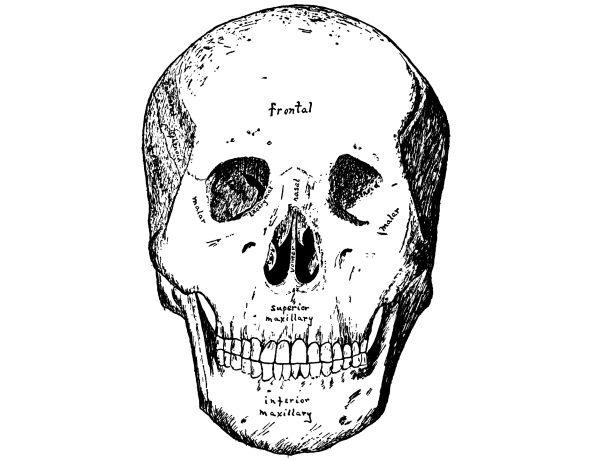

The intelligence and all the special senses, except the sense of touch already spoken of, are gathered together compactly in the head, where they are carefully protected with bony tissue. Covering the brain is the skull or cranium, which is made up of eight bones, the frontal, the occipital, two parietal, two temporal, the sphenoid, and the ethmoid, while the bones of the face are fourteen in number, two nasal, two superior maxillary, two lachrymal, two malar, two palate, two inferior turbinated, the vomer, and the inferior maxillary. For the most part the bones are arranged in pairs, one on either side.

The Cranial Bones.—The cranium or skull is especially adapted for the protection of the brain and the bones are flat and closely fitted to its surface. They have two layers of bone, the outer and the inner tables, of which the outer is the thicker, and between these is a tissue filled with blood-vessels, the diploë. In the infant, whose brain has not yet attained its full size, opportunity must be left for growth and the skull therefore consists of a number of bones with interlocking notched edges, where growth takes place, but in the adult it forms one solid covering of bone.

The frontal bone, as its name implies, forms the fore part of the head or forehead. It joins the parietal bones above and the temporal bones on either side. At the lower edge are the supra-orbital arches, each with a supra-orbital notch or foramen on its inner margin for the passage of the supra-orbital vessels and nerve, the nerve most affected in neuralgia. Just above the arches on either side are the superciliary ridges, behind which, between the two tables of the skull, lie the frontal sinuses. On the inner surface the frontal sulcus for the longitudinal sinus runs along the median line.

The parietal bones are the side bones of the skull. They meet [Pg 50] each other in the sagittal suture at the median line above and join the frontal and occipital bones at either end, while below they touch upon the temporal bones, the temporal muscles being attached in part along their lower surface. These muscles are inserted into the coronoid process of the lower jaw, which they thus help to raise and to retract.

Fig. 16.—Front view

of the skull.

(After Sobotta.)